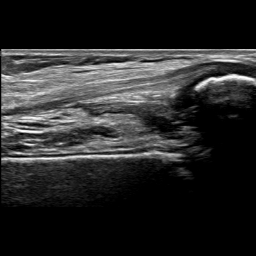

Figure 8 shows two US images that have been correctly classified by both approaches and that are relatively easy to classify by medical experts. Figure 8a shows an US image where the femur, the patella and the SQR are clearly visible, and the SQR is thin (i.e., not distended). On the other hand, Figure 8b shows an example of a Distended SQR. In this case, the SQR is clearly thick and hence distended.

Refer to caption

(a) Non-Distended SQR

(b) Distended SQR

Figure 8: Examples of images correctly classified by both solutions. The purple arrow points to the femur, the orange arrow points to the patella, and the green box indicates the SQR.